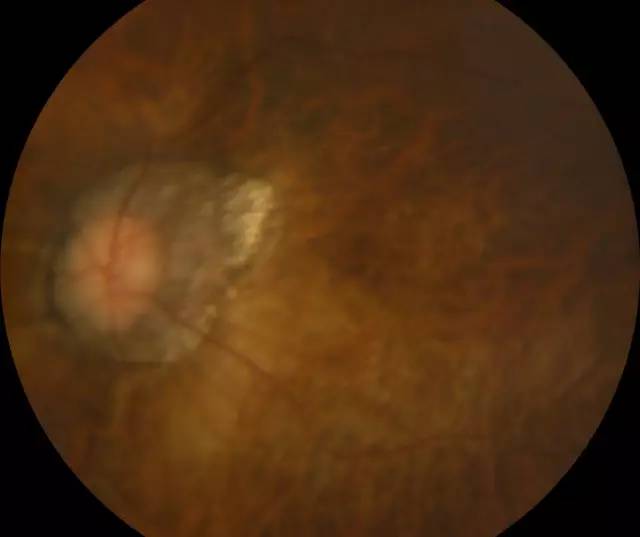

住院 几天后,赵铁英院长和医护团队给肖先生做了细致的术后检查,肖先生的视网膜已经 正常,左眼也终于能看清东西了。“如果我真的失明了,我觉得整个人生也完蛋了。真的很感谢赵院长,遇到这么好的医生,真的太幸运了!”肖先生不停的表达自己的感激之情。

肖先生左眼术后眼底照相图

赵院长在后来查房时讲到,类似这种超高度近视视网膜脱离的患者,因其视网膜和球壁非常薄弱,玻璃体结构异常,医治起来便非常困难, 率低,且复发率高,所以在选择手术方式时,要充分考虑患者的病情, 衡各种手术方式的利弊。